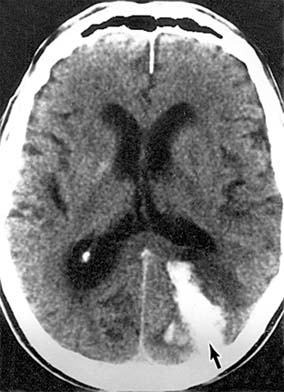

Chapter 14: Neuro-ophthalmology THE RETROCHIASMATIC VISUAL PATHWAYS Cerebrovascular disease and tumors are responsible for most lesions of the retrochiasmatic visual pathways, though almost any intracranial disease process can involve these structures. Retrochiasmatic visual field defects are homonymous. Partial lesions in the optic tract and lateral geniculate nucleus produce incongruous (or dissimilar) visual field defects due to a 90-degree medial rotation of axons in each tract and the decussation of half of the axons through the chiasm. Thus, there may be more involvement of a nasal hemifield than of its corresponding temporal hemifield. Once the lesion becomes complete, however, incongruity cannot be assessed, and this sign loses its localizing ability. Retrochiasmatic visual field defects should spare visual acuity since the visual pathway from the other hemibrain is intact. The optic tracts and lateral geniculate nucleus are infrequently affected. After several weeks to months, the disks may appear pale, and the retinal nerve fiber layer is deficient. The optic tract and lateral geniculate nucleus have at least a dual blood supply, so that primary vascular lesions are uncommon. Most cases are due to trauma, tumors, arteriovenous malformations, abscesses, and demyelinating diseases. Lesions involving the geniculocalcarine pathway to the occipital cortex produce homonymous field defects but do not result in optic atrophy (due to the synapse at the geniculate nucleus). Generally, the more posterior a lesion is located, the more congruous the homonymous visual field defect. The inferior geniculocalcarine pathway passes through the temporal lobe and the superior pathway through the parietal lobe, with macular function between them. Lesions of the inferior pathway result in superior visual field defects. Processes affecting the anterior and midtemporal lobes are commonly neoplastic; posterior temporal lobe and parietal processes can be either vascular or neoplastic. An insidious onset with mild and multiple neurologic deficits would be more typically neoplastic, whereas an acute cataclysmic neurologic event would be more typically vascular. Vascular lesions of the occipital lobe, on the other hand, are common and account for over 80% of cases of isolated homonymous visual field loss in patients over age 50 years. The most posterior tip of each occipital lobe projects to homonymous macular fields. Anterior to the macular representation lies the peripheral field; thus, vascular occlusions can selectively involve the posterior occipital cortex and produce homonymous defects with congruous macular scotomas or spare the posterior cortex, and homonymous defects with macular sparing will result. The cortical centers involved in the generation of optokinetic nystagmus lie in the area between the occipital and temporal lobes and in the posterior parietal area, which are within the vascular territory of the middle cerebral artery. Optokinetic nystagmus asymmetry characteristically occurs in parietal lesions but not in occipital lesions. An asymmetric optokinetic nystagmus combined with an occipital visual field defect indicates a process not respecting vascular territories and thus suggests a tumor (Cogan's sign). CT scans and MRI demonstrate cerebral lesions with remarkable clarity ( PREVIOUS | NEXT Page: 1 | 2 | 3 | 4 | 5 | 6 | 7 | 8 | 9 | 10 | 11 | 12 | 13 | 14 | 15 10.1036/1535-8860.ch14 |